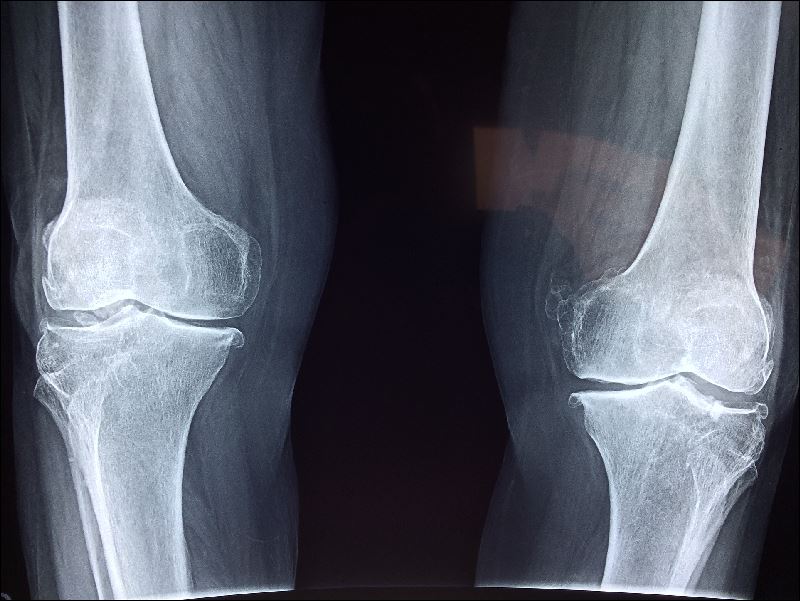

또는 뼈의 리모델링이라고도 합니다. 건강한 뼈에서는 뼈 흡수(뼈를 망가뜨리는 기능)와 뼈 형성(뼈를 만드는 기능)의 밸런스가 균형을 이루고 있습니다. 그러나 골다공증 뼈는 뼈 흡수가 점점 진행되어 뼈 형성을 웃돌아 버려 뼈가 스산해지고 약해집니다.

골다공증 유병률의 성별·연대별 폐경기 후 여성호르몬 저하 골다공증은 특히 여성에게 많은 질병으로 환자의 80% 이상이 여성으로 알려져 있습니다.

원인이 되는 대표적인 질병으로는 부갑상선 기능 항진증 등의 내분비 질환, 류마티스 관절염 외에 당뇨병을 비롯한 생활 습관병으로 빈도가 높은 것으로 알려져 있습니다. 이러한 질병에서는 뼈대사에 영향을 미치는 호르몬이 부족하거나 뼈형성에 필요한 세포 등에 이 상이 발생하여 골밀도가 줄어드는 경우도 있지만, 뼈 속에 골질을 열화시키는 물질이 많아져 뼈가 약해지는 경우도 있습니다.

4cm 이상 신장이 줄어든 사람은 적극적으로 골밀도 검사나 엑스레이 검사를 받도록 권장하고 있습니다.